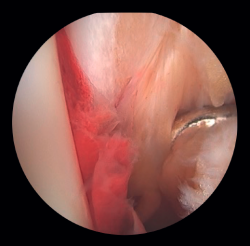

Arthroscopy assists ORIF in evaluating the congruence of the joint surface. It is especially useful for reduction of the medial malleolus. The malreduction rate in medial malleolus fractures is 22.2-32.6%(15,16). Initial arthroscopy allows us to determine whether tibial malleolus reduction can be performed in an open or closed manner. In cases with significant displacement, open synthesis is chosen, always maintaining arthroscopic control during the procedure to ensure precise reduction and avoid rotation of the distal fragment (Figure 4).

Patients at greatest risk of malreduction are those over 60 years of age, due to decreased bone quality and more complex fractures(17). Patients with open fractures and fracture dislocations have a 2.15 to 2.7 times higher risk, respectively, due to increased soft tissue damage and fracture complexity. Vertical fractures and with interposed soft tissues make it difficult to achieve anatomical reduction(15,16).